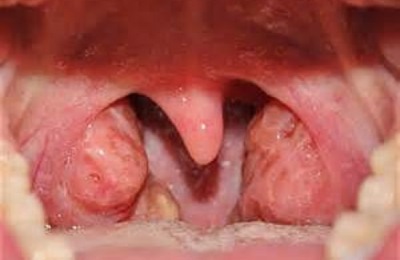

Имеющий длительное течение воспалительный процесс, локализированный в глоточных и небных миндалинах, принято называть тонзиллитом. Данное заболевание зачастую проявляется после перенесенной инфекционной болезни, способной вызывать поражение слизистой оболочки зева и может вызываться разными вирусными и бактериальными агентами.

Чаще всего причина болезни – бета гемолитический стрептококк группы А, что обуславливает внушительный список достаточно серьезных осложнений, возможных при отсутствии адекватного лечения.

Проявляться хронический тонзиллит может следующими симптомами:

Практически полное отсутствие специфических жалоб может стать причиной несвоевременного выявления патологии, и, как следствие, сделать возможным развитие многих опасных осложнений, таких как ревматизм, гломерулонефрит или паратонзиллярный абсцесс.